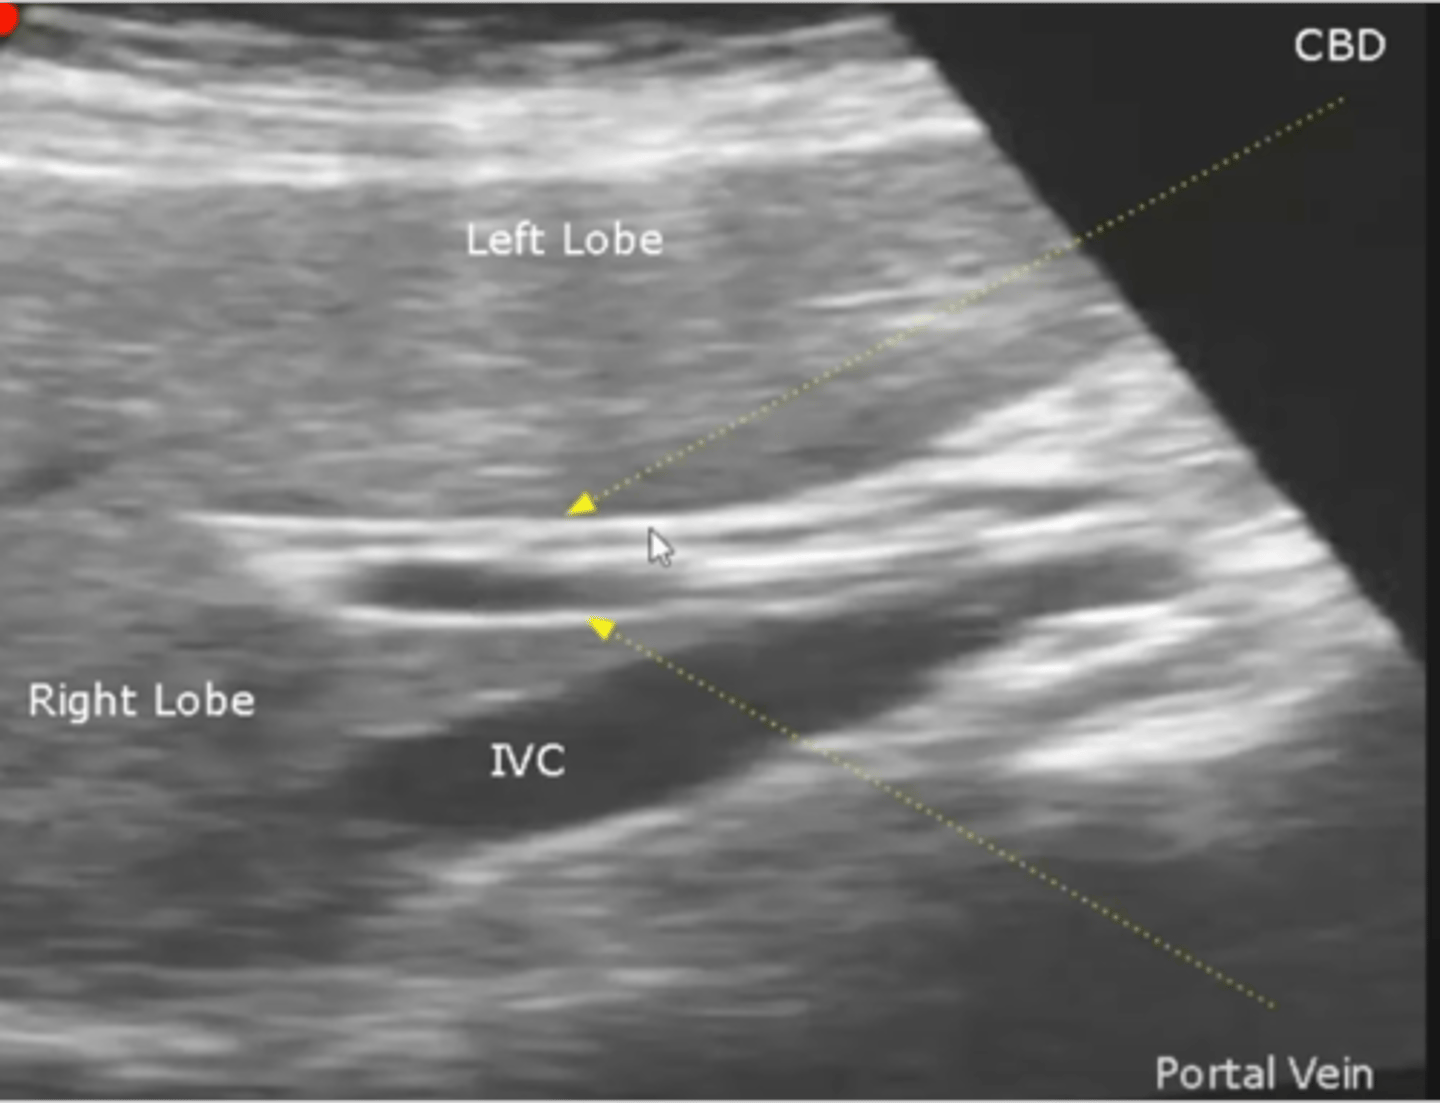

Portahepatis and bile duct on US